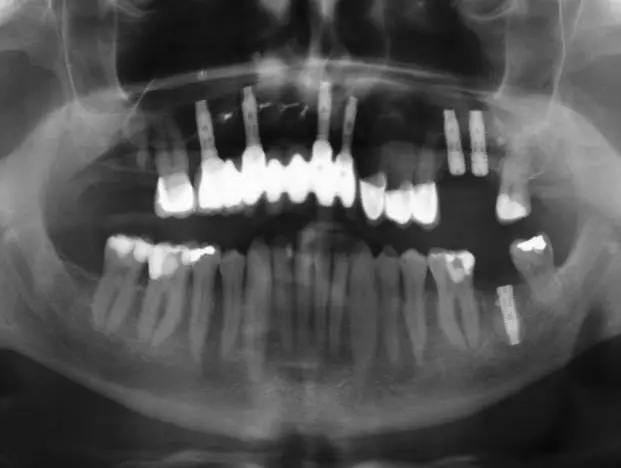

Nach dem Entfernen der insuffizienten Versorgung von 14 auf 22, stellten sich die Zähne 14, 13, 21 und 22 als nicht erhaltungswürdig heraus. Präoperativ wurde ein Eierschalenprovisorium gefertigt, welches im März 2015 auf den Zähnen 15 und 23 sowie auf temporären Implantaten regio 013, 014, 021 und 022 (Bone Trust® mini, Medical Instinct, Bovenden) intraoperativ angepasst und verankert werden sollte (vgl. Abb. 8-13). Im Verlauf des Eingriffs, bei dem die genannten Zähne operativ entfernt wurden, zeigten sich ausgedehnte radikuläre Zysten, die mit einer Resorption der vestibulären Knochenlamelle einhergingen und ektomiert werden mussten (Abb. 4-6).

Auf dieser Grundlage ergab sich der folgende Behandlungsplan:

- Juli 2018: Transplantation eines durch digitalisierte Planung individuell an die Defektregion des Patienten angepassten allogenen Knochenblocks (Abb. 15).

- Januar 2019: Insertion von definitiven Implantaten im allogenen Knochenblocktransplantat regio 015, 013,021,022 sowie direkter Sinuslift regio 026 und 027.

- Juni 2019: Operative Freilegung 015, 013, 021, 022 und Implantation regio 026, 027.

- Februar-März 2020: Freilegung regio 026, 027, prothetische Versorgung des Oberkiefers, Implantation 037.

Operationsprotokoll II – Januar 2019

Nach sechsmonatiger Einheilzeit des Augmentats (Abb. 22 und 23) erfolgte im Januar 2019 das Re-Entry (Abb. 24). Die Mikrofixturen/Osteosyntheseschrauben wurden entfernt und vier definitive Implantate (T3, Zimmer Biomet Dental) mit einem Drehmoment von 30 Ncm nach vorherigem Gewindeschneiden (Abb. 25) inseriert: regio 015 (4,0 mm x 13 mm; simultaner direkter Sinuslift), 013 (4,0 mm x 13 mm), 021 (4,0 mm x 13 mm), 022 (3,25 mm x 13 mm). Der Knochenblock zeigte eine gute Osseointegration und Vaskularisierung, lediglich in regio 012 war er leicht gelockert, jedoch periostal gestielt (Abb. 26).